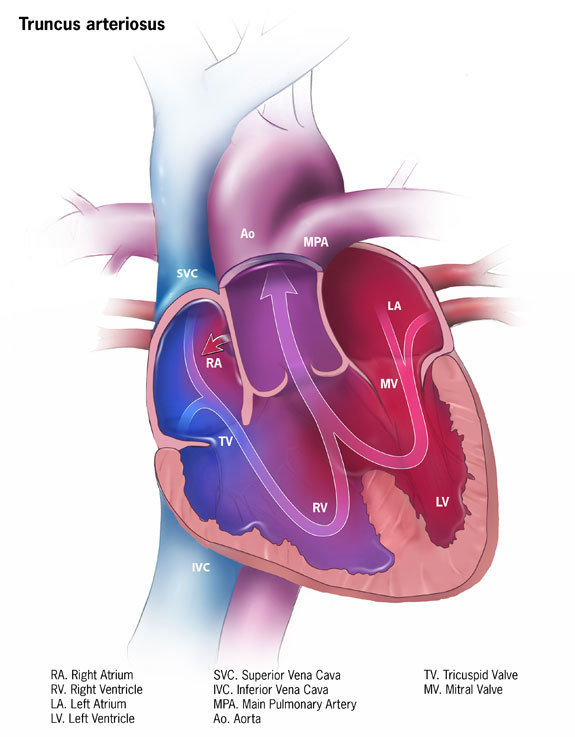

Persistent truncus arteriosus

This happens when the embryological structure known as the truncus arteriosus fails to properly divide into the pulmonary trunk and aorta, leaving the appearance of an underdeveloped septum.

This means oxygenated blood and deoxygenated blood can mix within the heart, causing this mix of blood to circulate the body.

- Close the hole between the two ventricles with a patch

- Separate the upper portion of the pulmonary artery from the single large vessel

- Implant a tube (conduit) and valve to connect the right ventricle with the upper portion of the pulmonary artery — creating a new, complete pulmonary artery

- Reconstruct the single large vessel and aorta to create a new, complete aorta